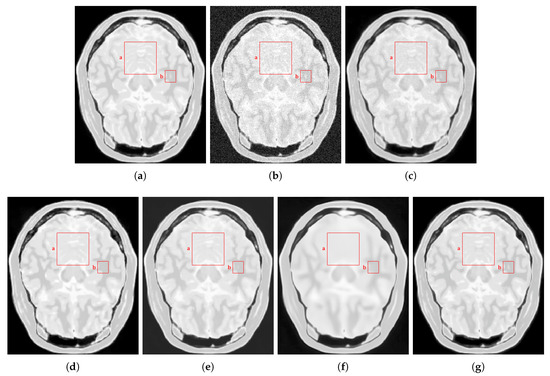

4.2.1. Synthetic Data

4.2.2. Real Data